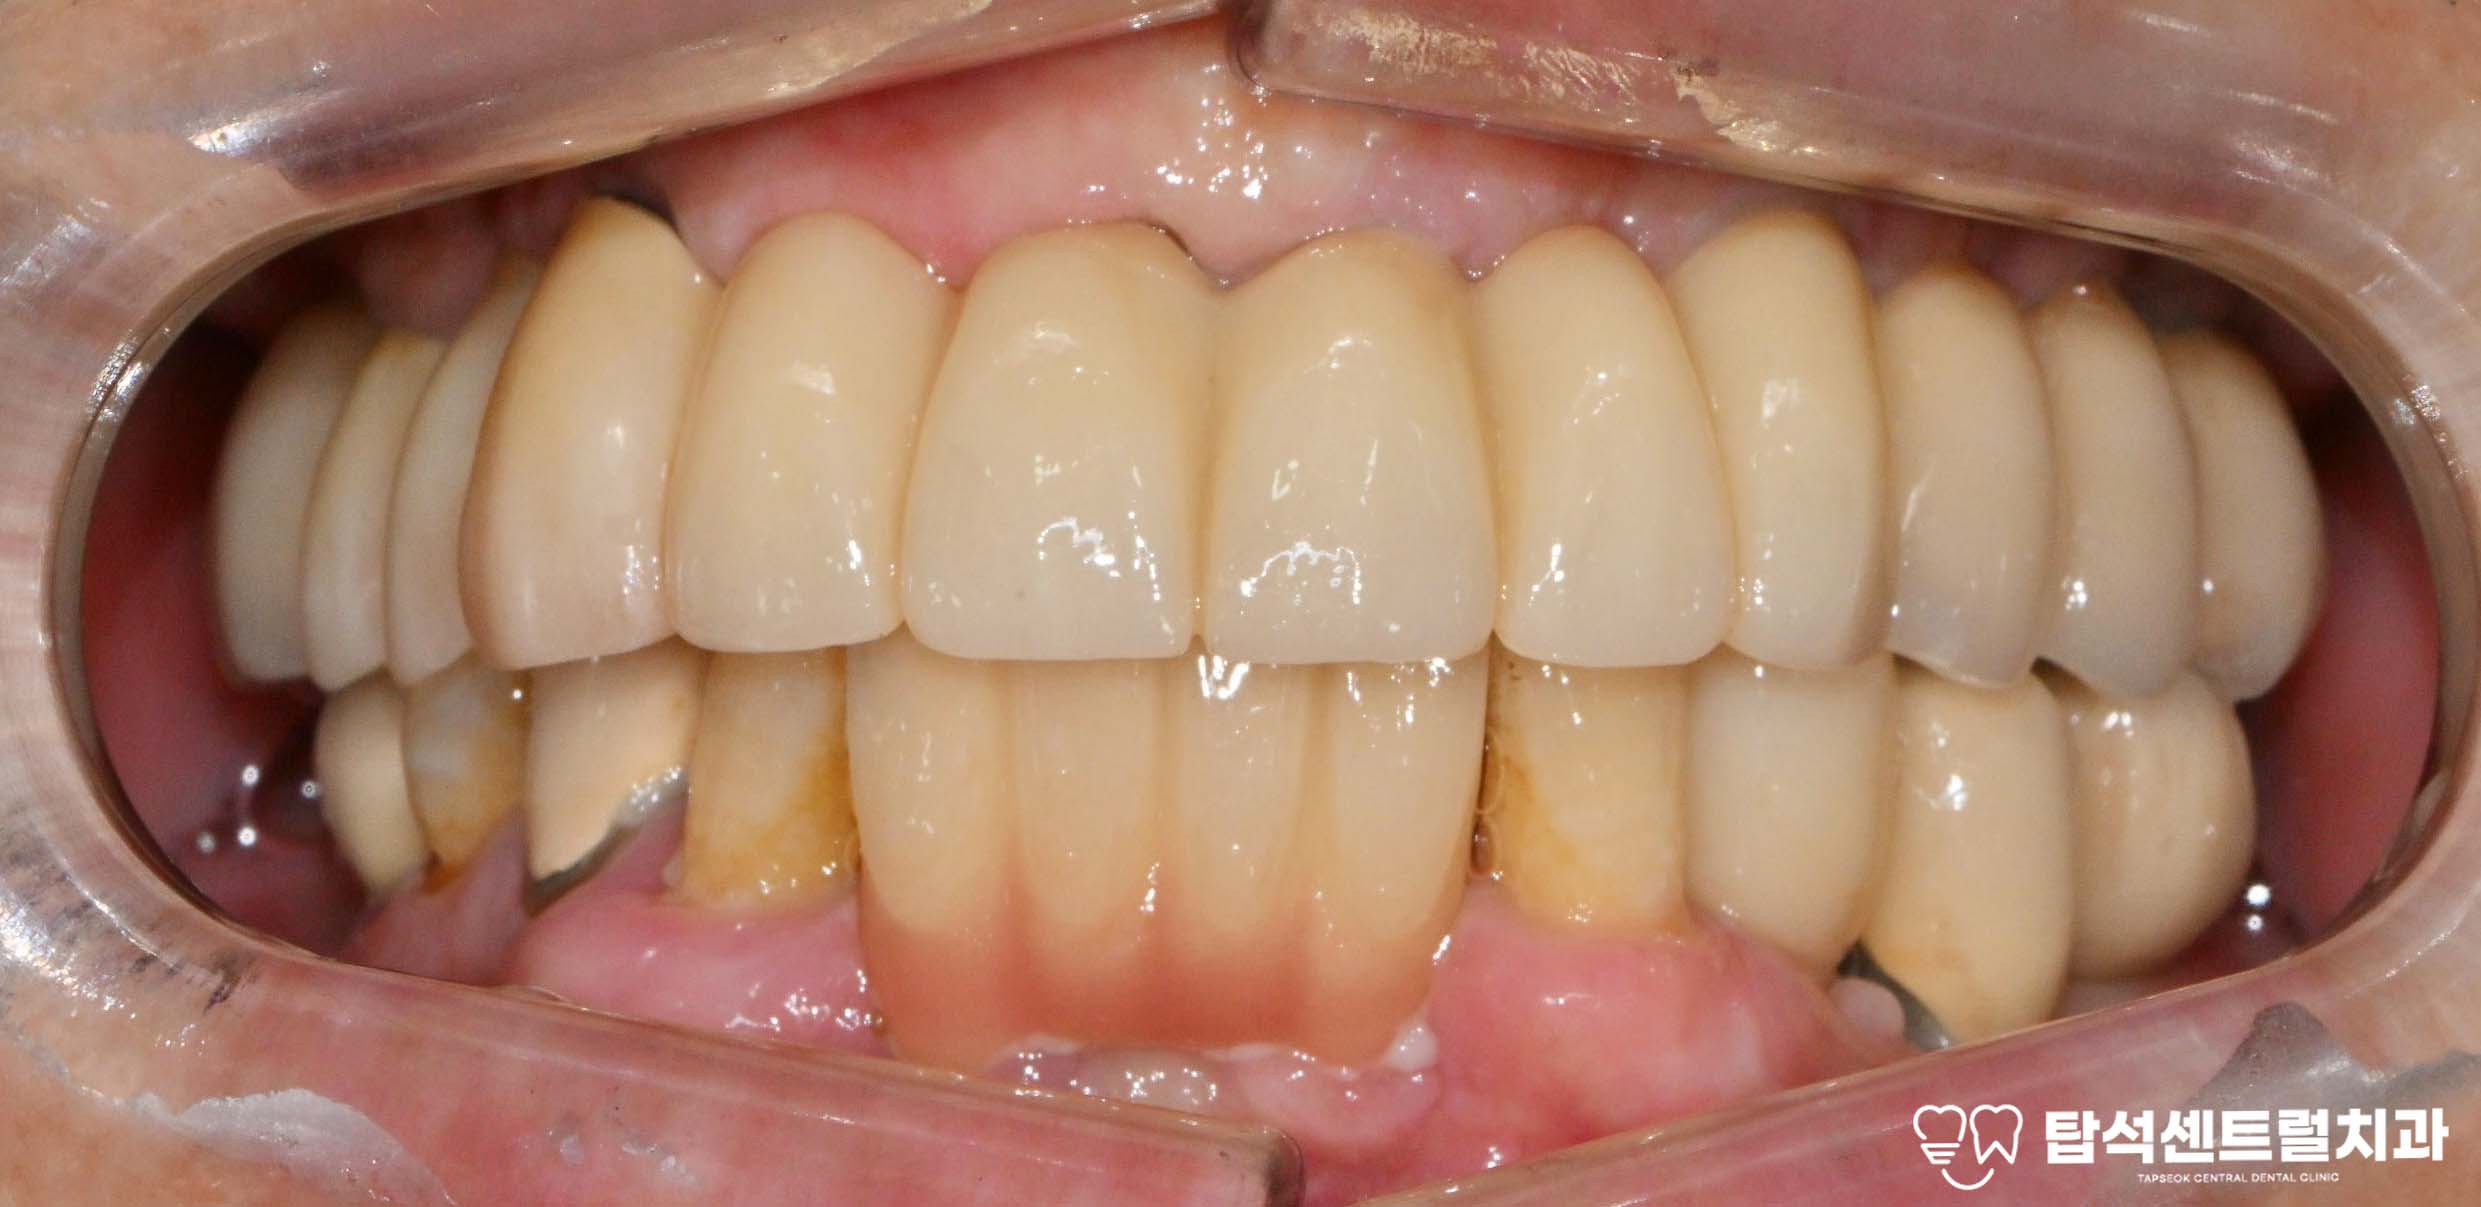

이후 잇몸이 회복되면 제작할 보철의

색을 고릅니다.

자연스러운 색으로 제작하여야,

보철을 올렸을 때도

어색한 느낌 없이 조화로워 보입니다.

최종 보철을 제작하기 전까지

임시 치아를 올려 심미성과

저작 기능을 잃지 않도록 합니다.